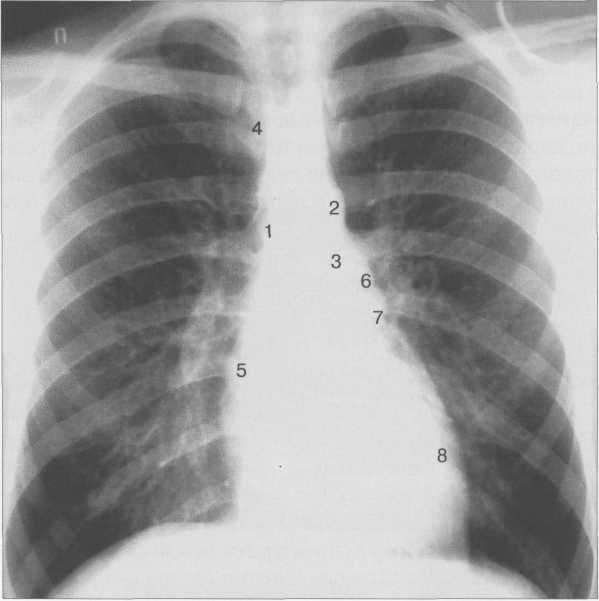

Рис. 9.24. Рентгенограмма грудной клетки. Передняя проекция.

1 — восходящая часть аорты; 2 — дуга аорты; 3 — нисходящая часть аорты; 4— верхняя полая вена; 5 — правое предсердие; 6 — легочный ствол; 7 — ушко левого предсердия; 8 — левый желудочек.

Состояние отдельных полостей сердца и крупных сосудов оценивается с помощью анализа краеобразующих дуг сердца (рис. 9.24).

Правый контур образован двумя дугами: восходящая часть аорты и правое предсердие. Точка их пересечения носит название правого атриовазального угла. Протяженность первой и второй дуг должна быть одинаковой. У новорожденных правый желудочек имеет относительно большие размеры, поэтому протяженность второй дуги больше (см. рис. 9.22).

Левый контур образуют 4 дуги: дуга аорты, легочный ствол, ушко левого предсердия, левый желудочек. В детском возрасте (приблизительно до 7 лет) протяженность дуги легочного ствола преобладает над протяженностью дуги аорты, в дальнейшем протяженность дуг становится одинаковой. У подростков и людей астенического сложения дуга легочного ствола выпрямленная или выпуклая (см. рис. 9.23), у взрослых она, как правило, вогнутая. Левая граница сердца на уровне левого желудочка находится на уровне среднеключичной линии или на 1 см кнутри от нее.